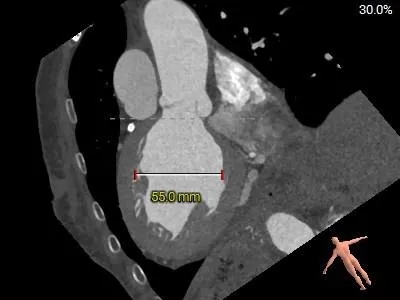

术前CT分析

主动脉根部测量

瓣上结构测量

瓣上2mm

23.7mm

瓣上4mm

24.1mm

瓣上6mm

24.6mm

瓣上8mm

24.3mm

冠脉风险评估

LCA:9mm

RCA:14.8mm

左右窦瓣叶长度均可